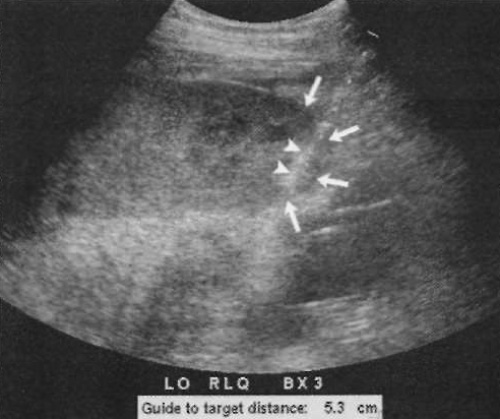

При подозрении на диффузное поражение естественной почки или на отторжение трансплантата забор биоптата проводят из нижнего полюса. Нужно выбирать место без прилегающих петель кишечника. Определить локализацию можно по длинной или короткой оси (поперечное сечение). Следует выбрать положение, при котором хорошо визуализируется корковое, а не мозговое вещество почки (фото 3).

Фото 3. Биопсия трансплантата почки. Указателями обозначена игла, которая проходит по периферии через нижний полюс (отмечен стрелками), откуда производят забор биоптата коркового вещества

ВАЖНО!!! При расчете направления прохождения иглы относительно капсулы почки необходимо учитывать, что первые 5-7 мм иглы являются мертвым пространством.

Перед началом процедуры проводят местное обезболивание, в том числе и капсулы почки. Во время забора биоптата из естественной почки пациент должен задерживать дыхание.